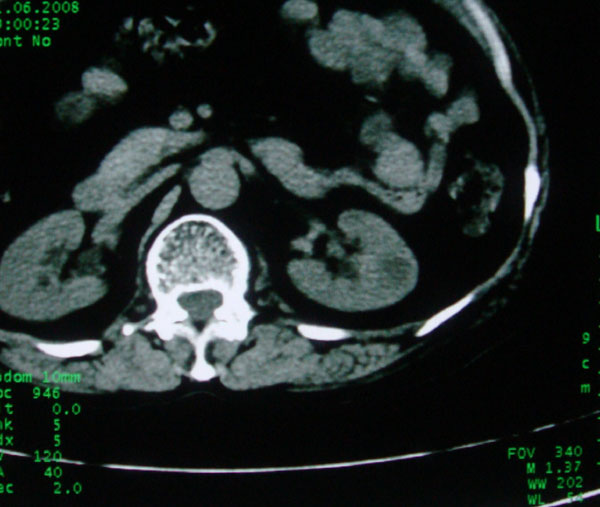

患者女性体查.发现左肾有低密度影,大家考虑是什么.其它方面没有什么异常.低密度影ct值约22hu.

左肾低密度影,境界尚清,查体发现,临床无其他首先考虑肾囊肿,如果增强一下对鉴别有帮助。

左肾不均匀低密度,其形态不规则、边界不清楚,更谈不上锐利。虽无局部凸出,但最后一张片显示仍有比较明显的隆起,我多考虑为肾癌,建议增强或mri检查。

左肾肾实质内低密度灶,性质待定。建议:行进一步检查。